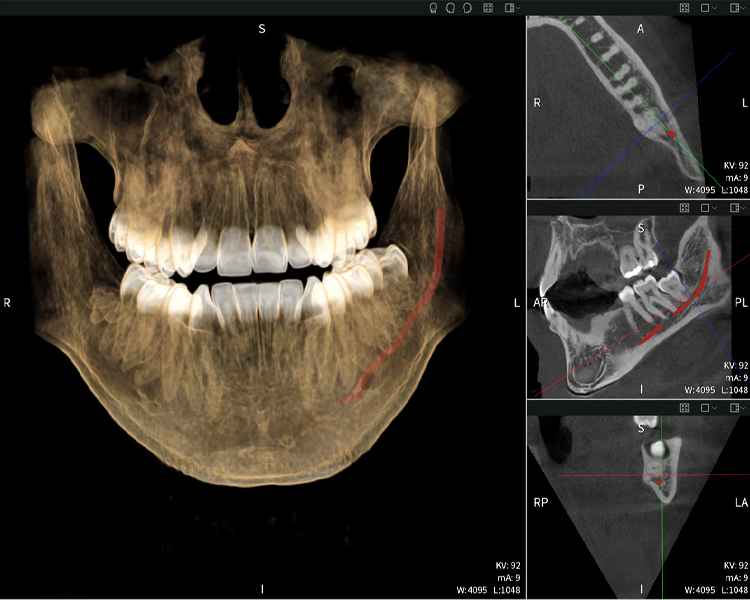

Below you will find a case from Dr. med. dent. Oliver A. Centrella, in which the CBCT images obtained with Seethrough Max provided crucial information on the complex anatomy and the critical relationship between the wisdom teeth and the inferior alveolar nerve. In this case, there is a indication for the surgical removal of the wisdom teeth.

Figures b–d show various views of a 3D reconstruction of the mandible, providing a comprehensive overview of the mandibular anatomy, the position of the nerves in relation to the teeth, and allowing assessment of tooth symmetry and alignment.

Figure d shows the previously treated tooth 48, with its crown removed, and its roots left in proximity to the nerve, illustrating the high risk of nerve damage.